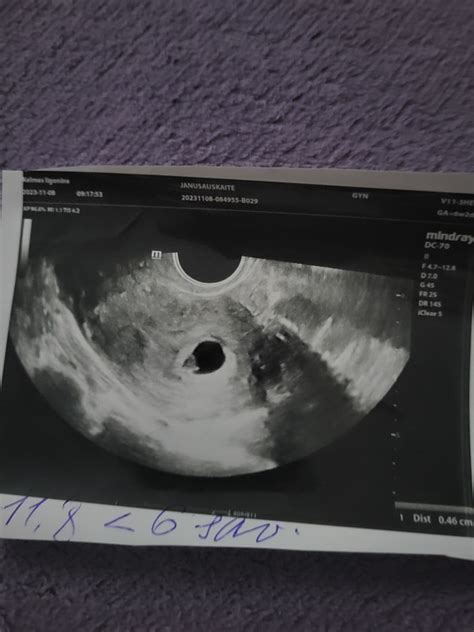

- Ankstyvoji echoskopija. Nėštumą galima nustatyti ir atlikus ankstyvąją echoskopiją. Tiesa, ankstyvoji echoskopija retai atliekama siekiant tiesiog patvirtinti nėštumą.